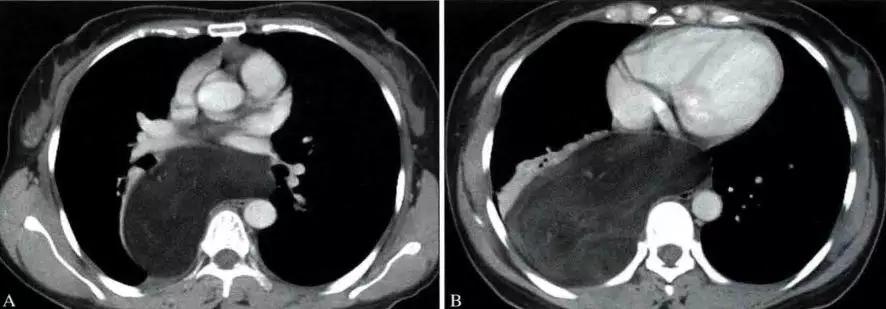

非侵袭性胸腺瘤CT图像

a. CT平扫示前上纵膈主动脉弓与胸骨间软组织密度肿块,密度均匀,边缘浅分叶状 b. CT增强示肿块均匀强化,肿块与主动脉弓之间脂肪间隙清晰

侵袭性胸腺瘤CT图像

a. CT平扫示肺动脉与胸骨间肿块,密度尚均匀,形态不规则b. CT增强示肿块不均匀强化,见低密度囊变区域,肿块与肺动脉之间脂肪间隙消失,肺动脉壁模糊。